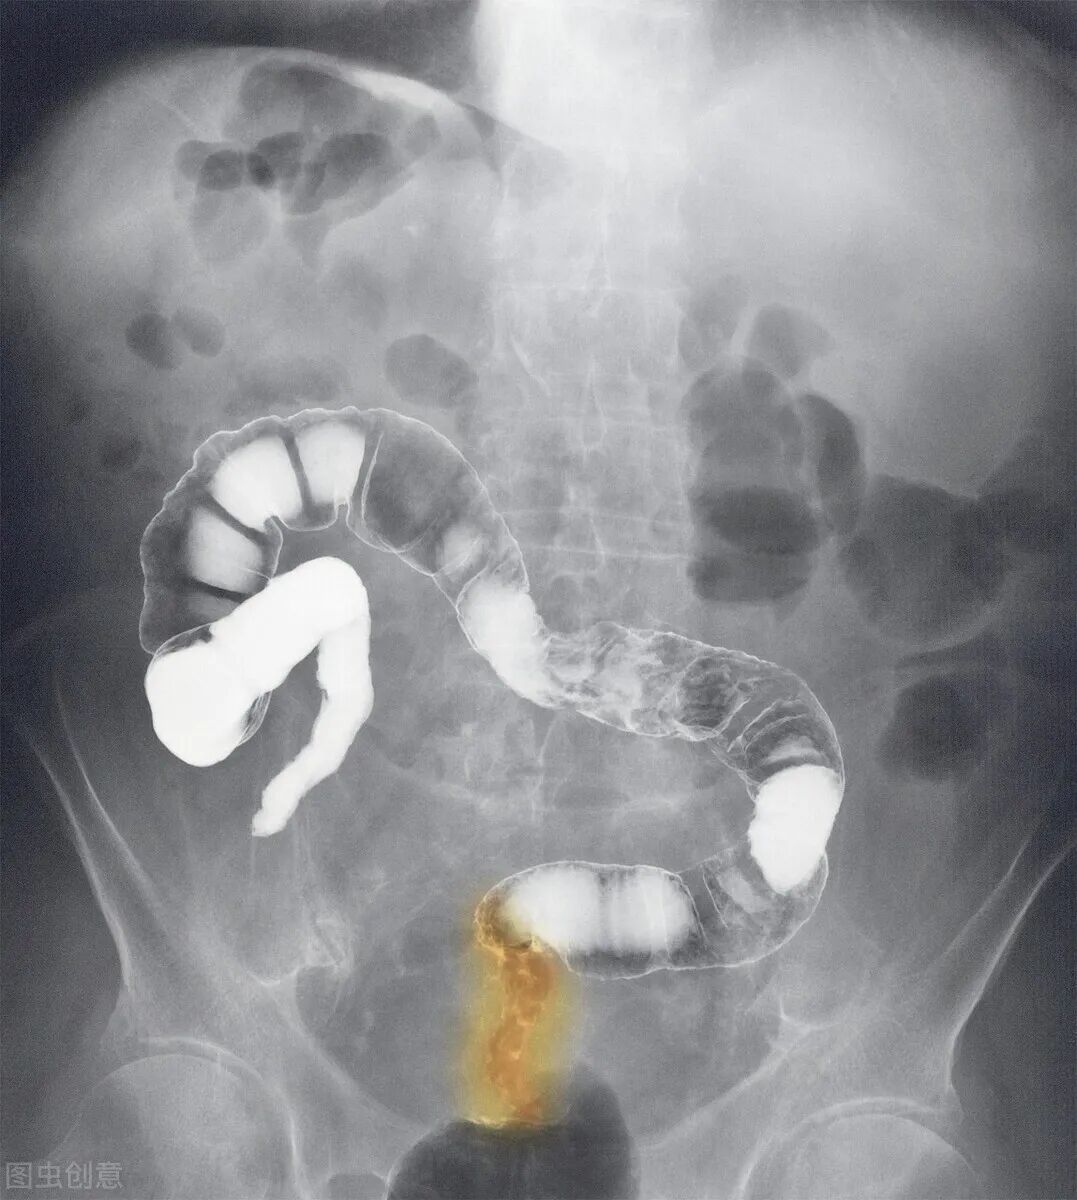

在进一步做筛查后,大家发现,王磊教授患的是癌中之王胰腺癌,并且已经到了晚期。